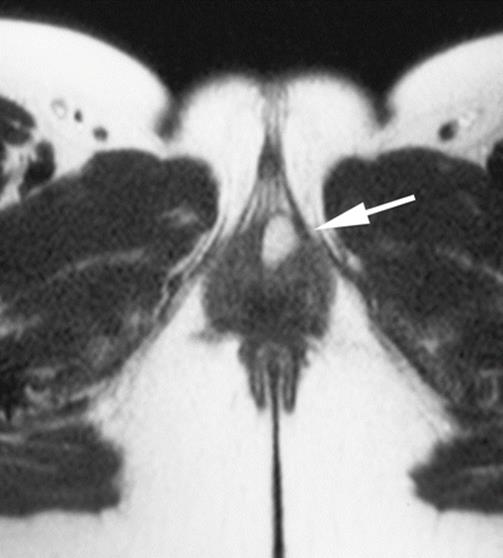

Fig. 8.3

Vaginal examination of the patient with a finger in the vagina under the right labia minora shows the cystic lesion in the inner aspect of the labia